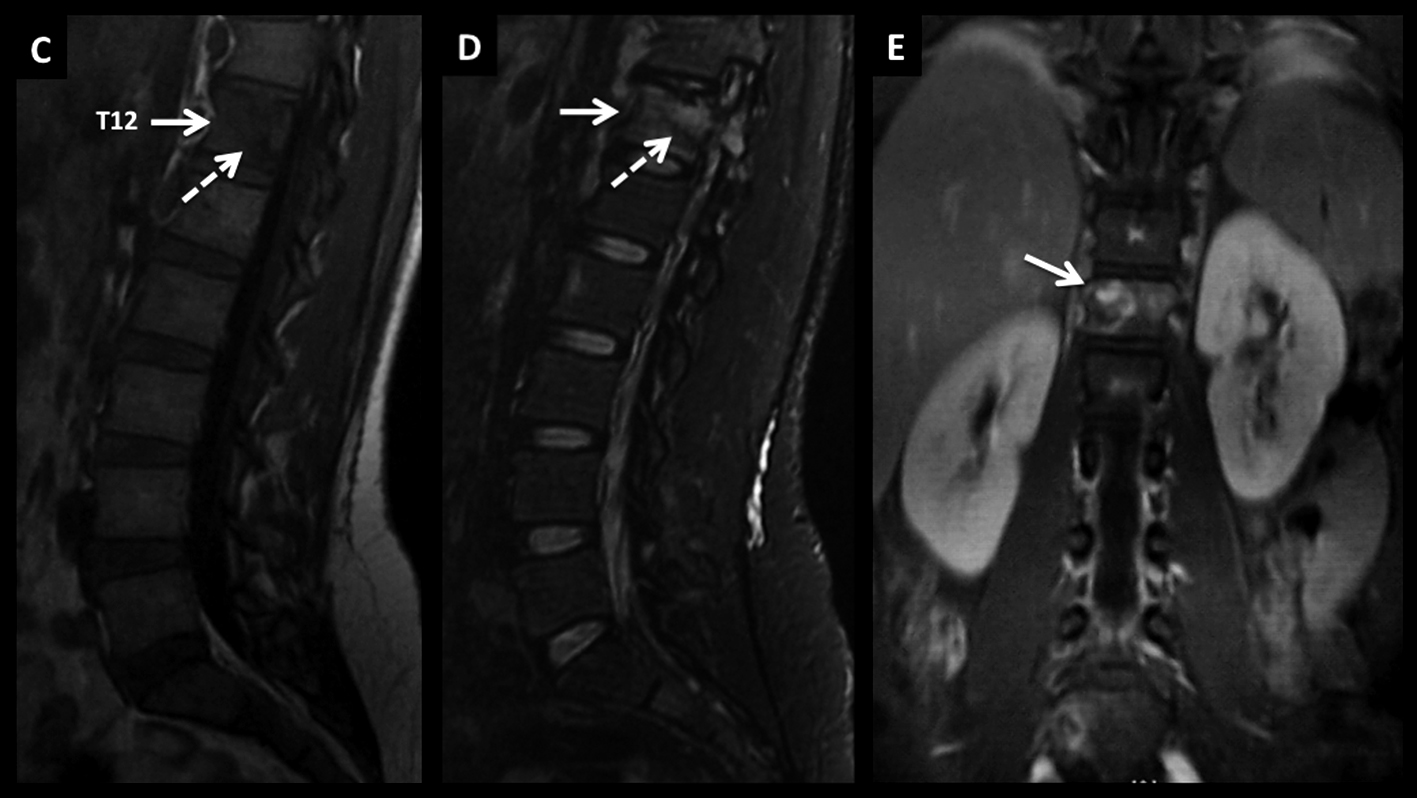

LNH, lesión medular, compromiso primario.

Paciente de 54 años con síndrome medular de instalación progresiva. En RM se identifica lesión medular cervical con ensanchamiento focal de varios segmentos, con alta intensidad de señal en secuencia T2 (A) y realce lineal, intenso, en secuencia T1 post-gadolinio (B).

Figura 8

LNH, lesión medular, compromiso primario. (cont)

En secuencia T2 en el plano axial (C) la alteración es heterogénea, centro-medular. Se decidió realizar biopsia de este proceso y el estudio histopatológico confirmó el diagnóstico de linfoma. Luego de la valoración sistémica no se evidenció compromiso asociado en otros territorios por lo que el diagnóstico final fue de LNH primario.